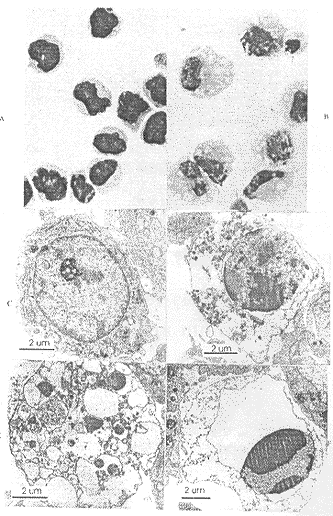

2.2 rhIL-6诱导M1细胞分化后凋亡 M1向巨噬细胞分化后,在rhIL-6诱导下走向凋亡。100ng/ml rhIL-6处理4d后,M1细胞Wright’s染色可见类似凋亡小体的结构(见图3)。且细胞DNA呈典型的梯状ladder(见图4)。由于DNA梯状ladder不能作为区分坏死与凋亡的特征性标志,我们又取10ng/ml、100ng/ml处理4~5d的细胞做了透射电镜观察。电镜下可见10ng/ml、100ng/ml处理4~5d时,约有10% 的细胞呈现凋亡各期的典型形态特征:染色质核膜下凝聚呈帽状、块状或月牙状,胞浆固缩,内质网扩张,胞浆空泡化——胞核及细胞外形皱缩,核裂解成质膜包绕的团块,即凋亡小体,电镜下凋亡小体的存在是确认凋亡发生最可靠的依据。对照组则没有上述特征的细胞,说明凋亡确由rhIL-6诱导产生。

图3 100ng/ml rhIL-6作用前后M1细胞的形态变化], http://www.100md.com

Fig3 Morphological changes of M1 cells induced by 100ng/ml rhIL-6], http://www.100md.com

A,C:normal control;B,D,E,F:incubation with rhIL-6 for 4d;A,B:wright’s staining(×1000);C,D,E,F:trans-mission electron micrograph